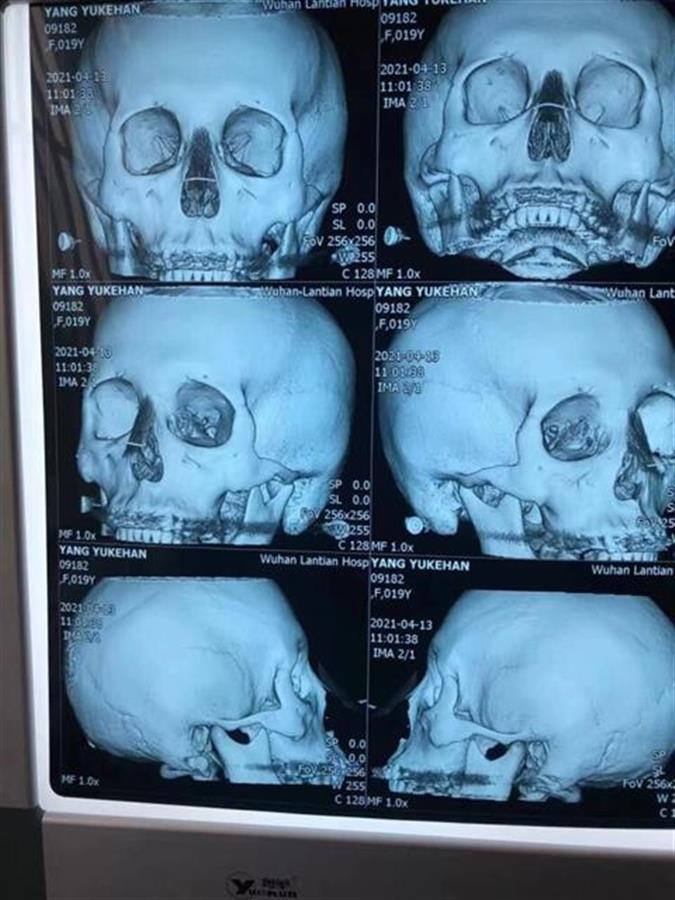

上周,王女士带着女儿到武汉一家权威的公立医院就诊,医生在对可可进行了全面检查后确认,其上次的整形手术存在问题,鼻部植入的假体出现了移位,需要再做手术进行修复,费用约8万元。随后,王女士带着女儿到武汉另外一家公立医院就诊,也得到了相似的结论。